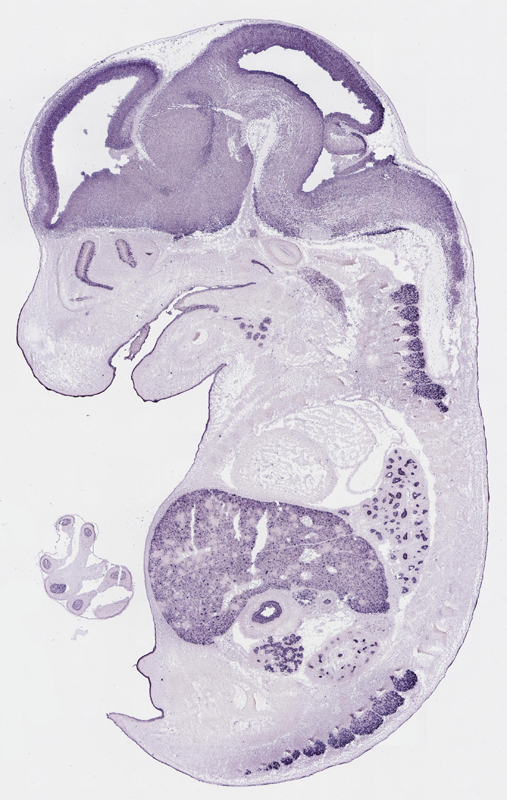

Specimen

euxassay_003287_02:

embryonic day 14.5